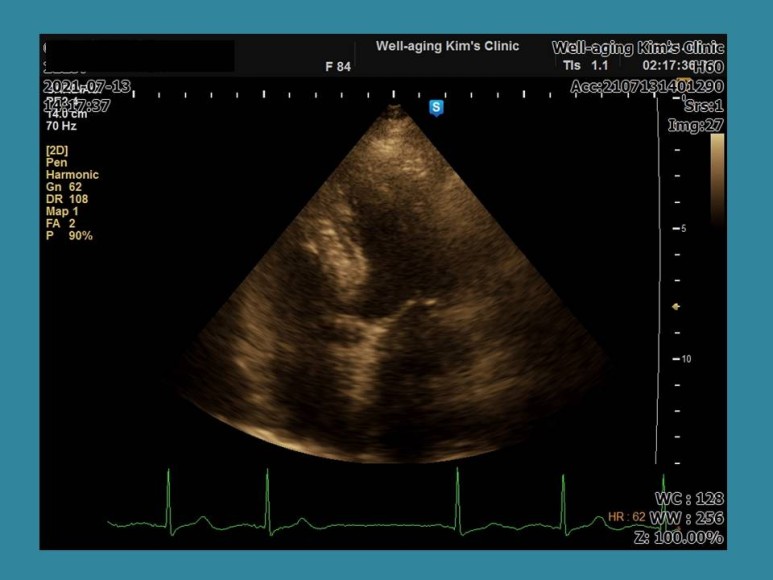

parasternal long axis view: 대동맥이 뻗어있고 흰 선처럼 움직이는 것이 찢어진 대동맥벽(대동맥 발리) 소견이다.칼로 후비는 듯한 심한 흉통을 호소하는 것으로 알려져 있으며 실제로 응급실을 방문해 이런 증상을 호소할 경우 대동맥 박리를 발견하는 경우가 많다.

둥근 원이 대동맥을 나타내고 그 안에 하안선처럼 움직이는 것이 대동맥벽이 찢어진 것(flap); 대동맥 박리소견이다.어차피 급박한 상황이기 때문에 환자와 보호자에게 상황설명 후 119 응급호출 후 상급병원으로 이송한 경우이다.

상행 대동맥에 흰 선이 움직이는 것이 대동맥이 박리된 상태.다음 증례는 83세 여성 환자로 성형외과 수술을 앞두고 수술 전 심장 평가를 위해 내원한 경우다.그쪽 병원에서 보내준 심전도는 정상이었지만.